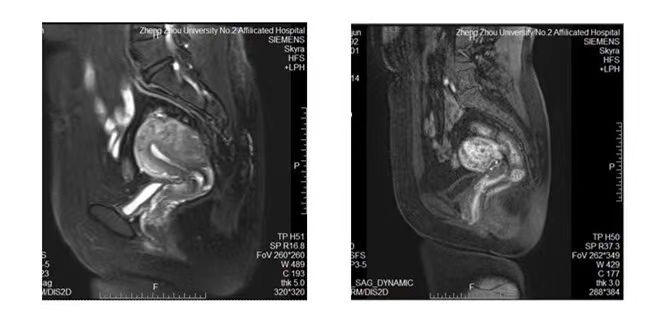

◆盆腔MRI:

子宫多发肌瘤,子宫下段后壁肌瘤变性或子宫腺肌瘤可能。